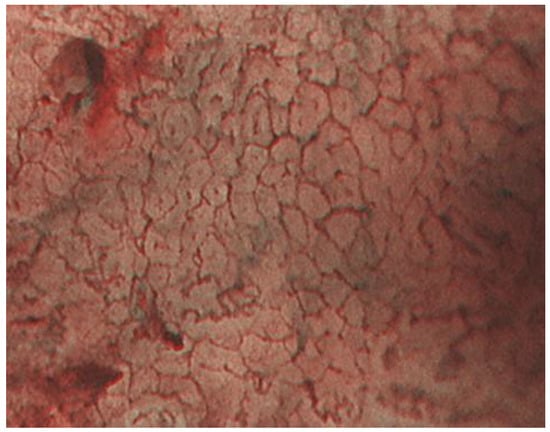

2.1. ME-NBI for Gastric Non-Cancerous Mucosa

- Kobayashi, M.; Hashimoto, S.; Nishikura, K.; Mizuno, K.; Takeuchi, M.; Sato, Y.; Ajioka, Y.; Aoyagi, Y. Magnifying narrow-band imaging of surface maturation in early differentiated-type gastric cancers after Helicobacter pylori eradication. J. Gastroenterol. 2013, 12, 1332–1342. [Google Scholar] [CrossRef]

- Saka, A.; Yagi, K.; Nimura, S. Endoscopic and histological features of gastric cancers after successful Helicobacter pylori eradication therapy. Gastr. Cancer 2016, 19, 524–530. [Google Scholar] [CrossRef]